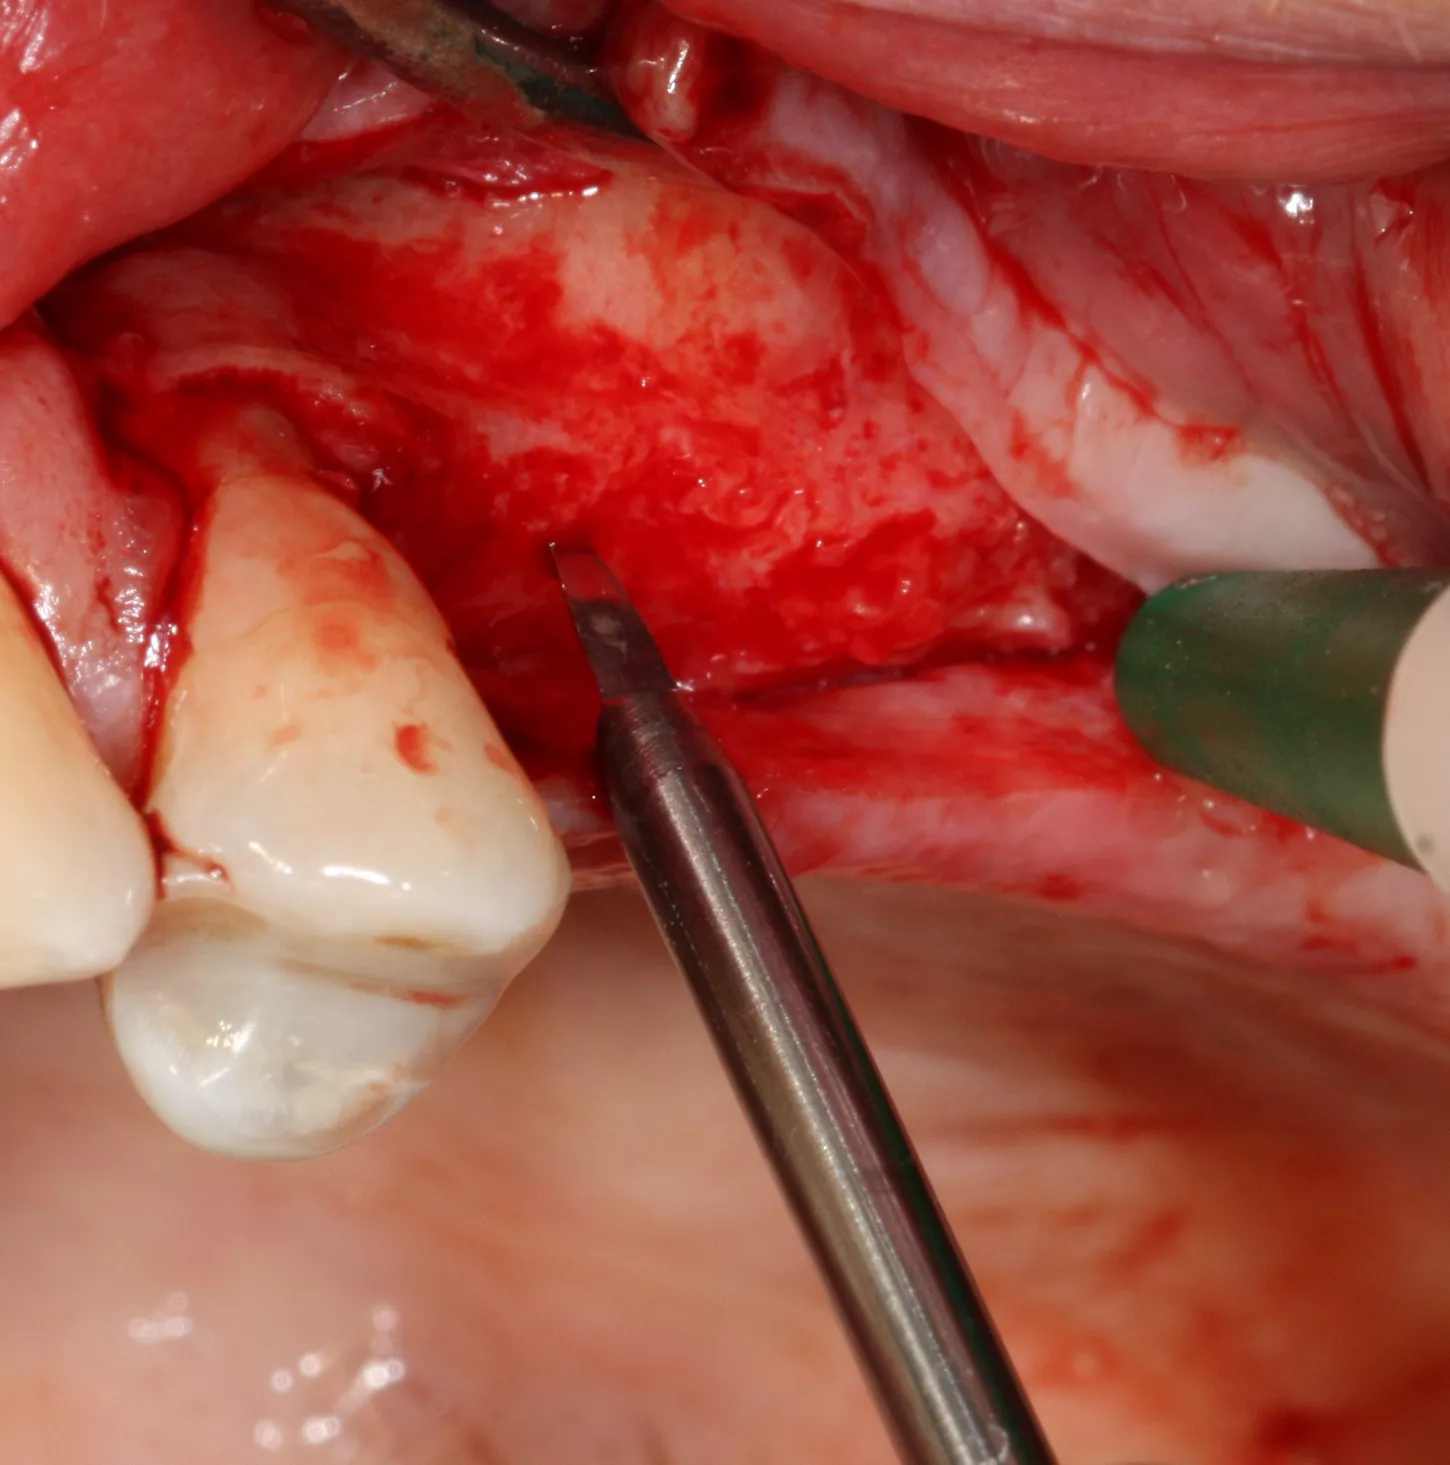

13. The implants were placed 0.5–1 mm subcrestally. Note the thinness of the vestibular cortical bone at the 25 implant on this occlusal view. Despite this, we achieved perfectly acceptable stability values of 19 and 20 Ncm.

14. Graft material added to the vestibular aspect of 25 to offset the bone loss and ensure long-term implant survival.